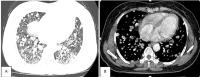

More than 40 different species of the parasitic flatworm Paragonimus have been identified worldwide, including in Vietnam, but only 10 species are known to cause disease in humans, particularly Paragonimus westermani. Paragonimus are transmitted through the ingestion of raw foods, especially freshwater shrimp, and crab. Paragonimiasis causes pneumonia, which can present as acute or chronic, with symptoms including prolonged cough, chest pain, shortness of breath, and hemoptysis. Hematologic changes include eosinophilia and the presence of specific antibodies for Paragonimus in the blood. Diagnosis is confirmed when Paragonimus specimens or eggs are found in the sputum or pleural fluid. The specificity of imaging is not high, but imaging can be used to guide the diagnosis. After the failure of microbiological diagnostic methods, lung biopsy can be used to confirm a diagnosis of paragonimiasis. We present a paragonimiasis case associated with unique features, including epidemiologic factors, atypical clinical signs, no increases in blood eosinophils, and negative microbiological tests. Although the patient was suspected of tuberculosis or lung cancer, imaging studies were consistent with the presence of lung flukes. Three transthoracic lung biopsies were performed, and pathology revealed a cystic structure containing Paragonimus on the third biopsy.